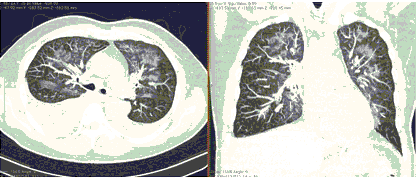

КТ имеет высокую чувствительность в выявлении изменений в легких, характерных для COVID-19. Применение КТ целесообразно для первичной оценки состояния ОГК у пациентов с тяжелыми прогрессирующими формами заболевания, а также для дифференциальной диагностики выявленных изменений и оценки динамики процесса. КТ позволяет выявить характерные изменения в легких у пациентов с COVID-19 еще до появления положительных лабораторных тестов на инфекцию с помощью МАНК. В то же время, КТ выявляет изменения легких у значительного числа пациентов с бессимптомной и легкой формами заболевания, которым не требуется госпитализация. Результаты КТ в этих случаях не влияют на тактику лечения и прогноз заболевания при наличии лабораторного подтверждения COVID-19. Поэтому массовое применение КТ для скрининга асимптомных и легких форм болезни не рекомендуется.

Вместе с тем, комплексная оценка анамнестических, клинических и рентгенологических данных позволяет определить клинически подтвержденный случай COVID-19, маршрутизировать пациента и начать противовирусную терапию.

2. Наличие клинических проявлений, указанных в п. 1, в сочетании с характерными изменениями в легких по данным компьютерной томографии (КТ) (см. Приложение 1 настоящих рекомендаций) вне зависимости от результатов однократного лабораторного исследования на наличие РНК SARS-CoV-2 и эпидемиологического анамнеза.